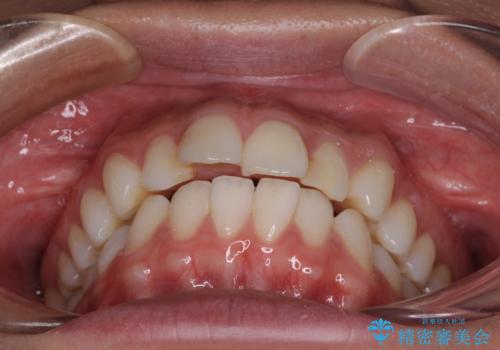

- くちばしのような前歯の突出感を気にして来院された患者様です。

上下左右第一小臼歯4本を抜歯して、積極的に口元を引っ込めるよう、ワイヤー装置にて矯正治療を行うこととしました。

抜歯矯正を行ったことで、顎先のつっぱり感や口元の閉じにくさを解消することができました。